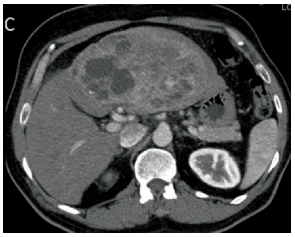

Paciente de 61 anos, sexo feminino, apresenta quadro de dor abdominal incaracterística há cerca de

2 meses, acompanhado de vermelhidão facial eventual, emagrecimento. O exame físico do abdome

parecia normal, com discreto aumento indolor do fígado. Sem sinais clínicos ou laboratoriais de icterícia.

Chega ao hospital já com propedêutica avançada, porém, ainda sem diagnóstico. Entre os exames,

há vários marcadores tumorais (CEA e CA 19-9 normais, cromogranina A elevada, e Ácido 5-Hidroxi

indolacético aumentado), enzimas hepáticas normais e uma tomografia computadorizada que gerou a

imagem abaixo: